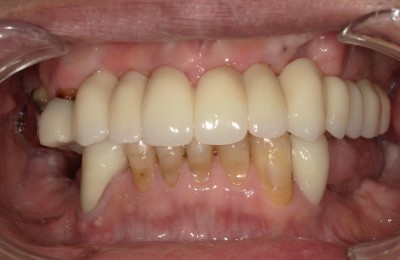

CASE01インプラント

Before

After

| 主訴 | 入れ歯以外の方法でしっかり咬みたい。 |

|---|---|

| 治療方法 | インプラントを6本埋入し、その上部をセラミックで作りしっかり咬めるようにした。 |

| 治療期間 | 約5カ月 |

| リスク | メンテナンスをしないことによるインプラント周囲炎、上部セラミックの破折。 |

| 費用 | 3,476,000円(税込) |